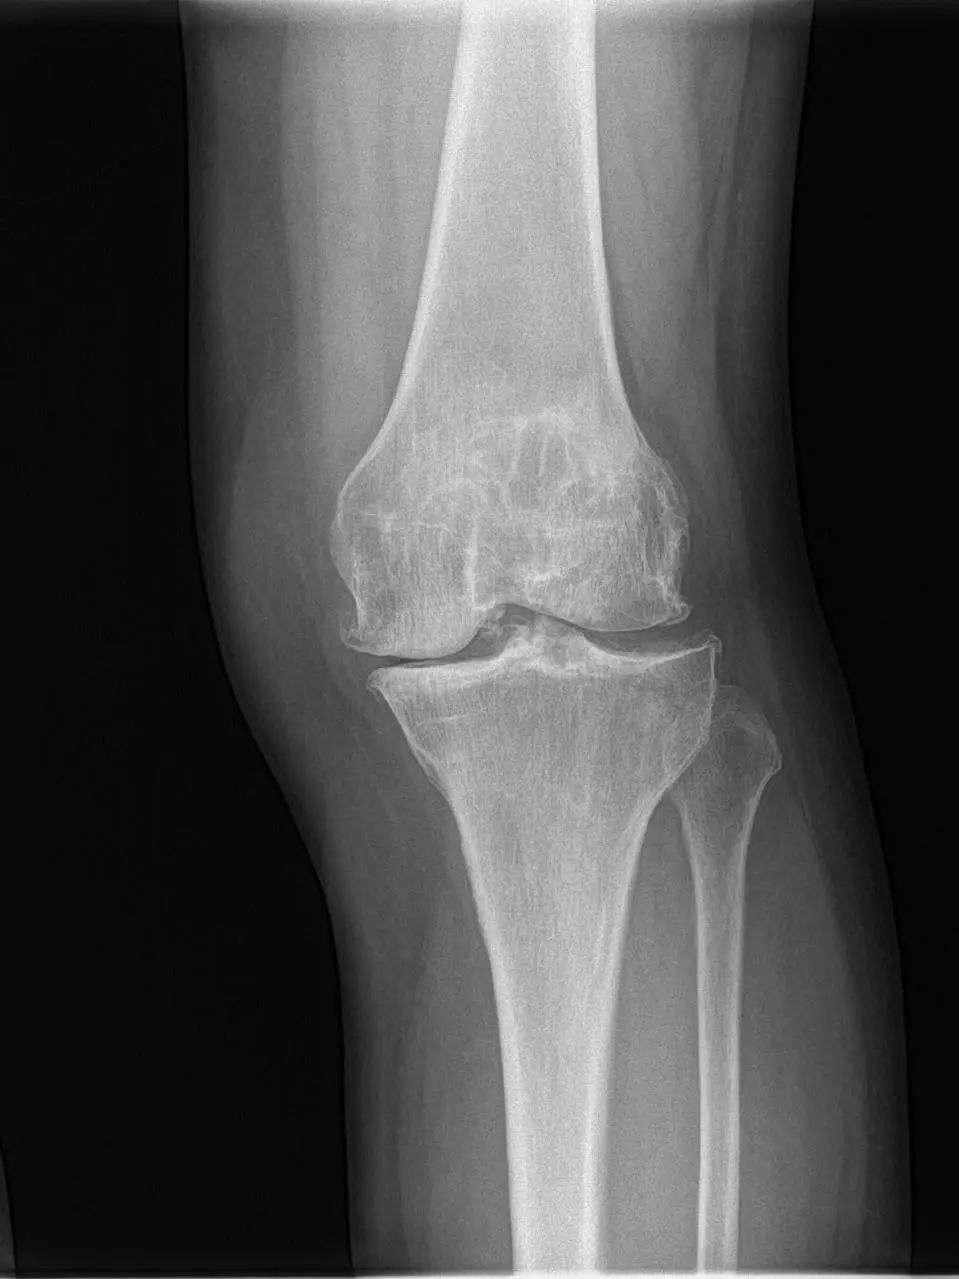

67岁的邵阿姨,双膝关节疼痛10余年,疼痛主要集中在屈伸膝关节时髌骨下。长期口服及外用药物治疗效果欠佳,反复加重,双膝的x线检查提示主要为髌股关节的退行性骨关节炎。程飚主任结合患者症状,影像学结果,体格检查,发现邵阿姨主要问题集中在髌股关节,膝关节间隙,内外侧髁,胫骨平台均可,为解决邵阿姨痛苦,尽可能保留关节,程飚主任决定对邵阿姨进行双侧膝关节的髌股关节表面置换,截骨量较少,邵阿姨第二天就能下地活动了,屈伸关节也不痛了,对手术疗效表示非常的满意。